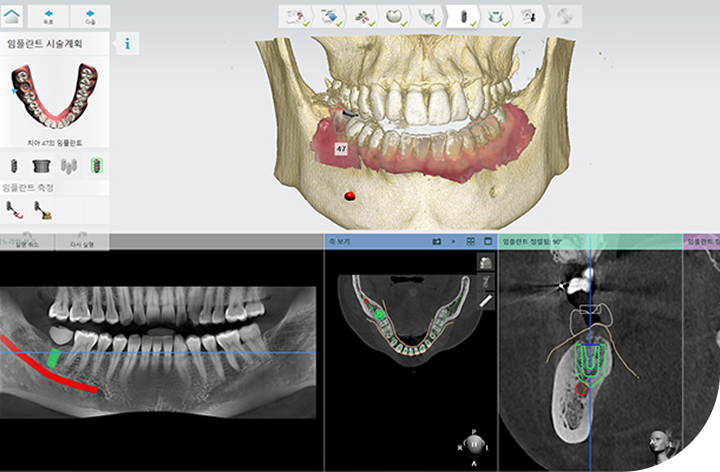

환자의 구강 정보를 디지털 데이터를 기반으로 3D 가상 모의 수술을

진행해 기존 방식 대비 수술 시간이 짧아 체력적 부담을 줄여주고

최소 절개로 통증 및 붓기 최소화로 면역력이 약하거나 회복력이 더딘

고령의 환자, 고혈압 당뇨 등 전신질환을 앓고 계신 분들도 부담없이 안전하게 수술받을 수 있습니다.

다양한 디지털 진단 장비를 활용

오차 줄인 안전한 진료

성공적인 임플란트 식립을 위해서는 정밀한 진단이 필수적입니다.

3D-CT, 구강 스캐너 등 다양한 디지털 장비를 이용하여

치아, 잇몸뼈, 신경 위치 등을 정확하게 파악해 수술 오차를 최소화하고,

통증 및 출혈을 줄여 더욱 안전하고 편안한 임플란트 식립이 가능합니다.